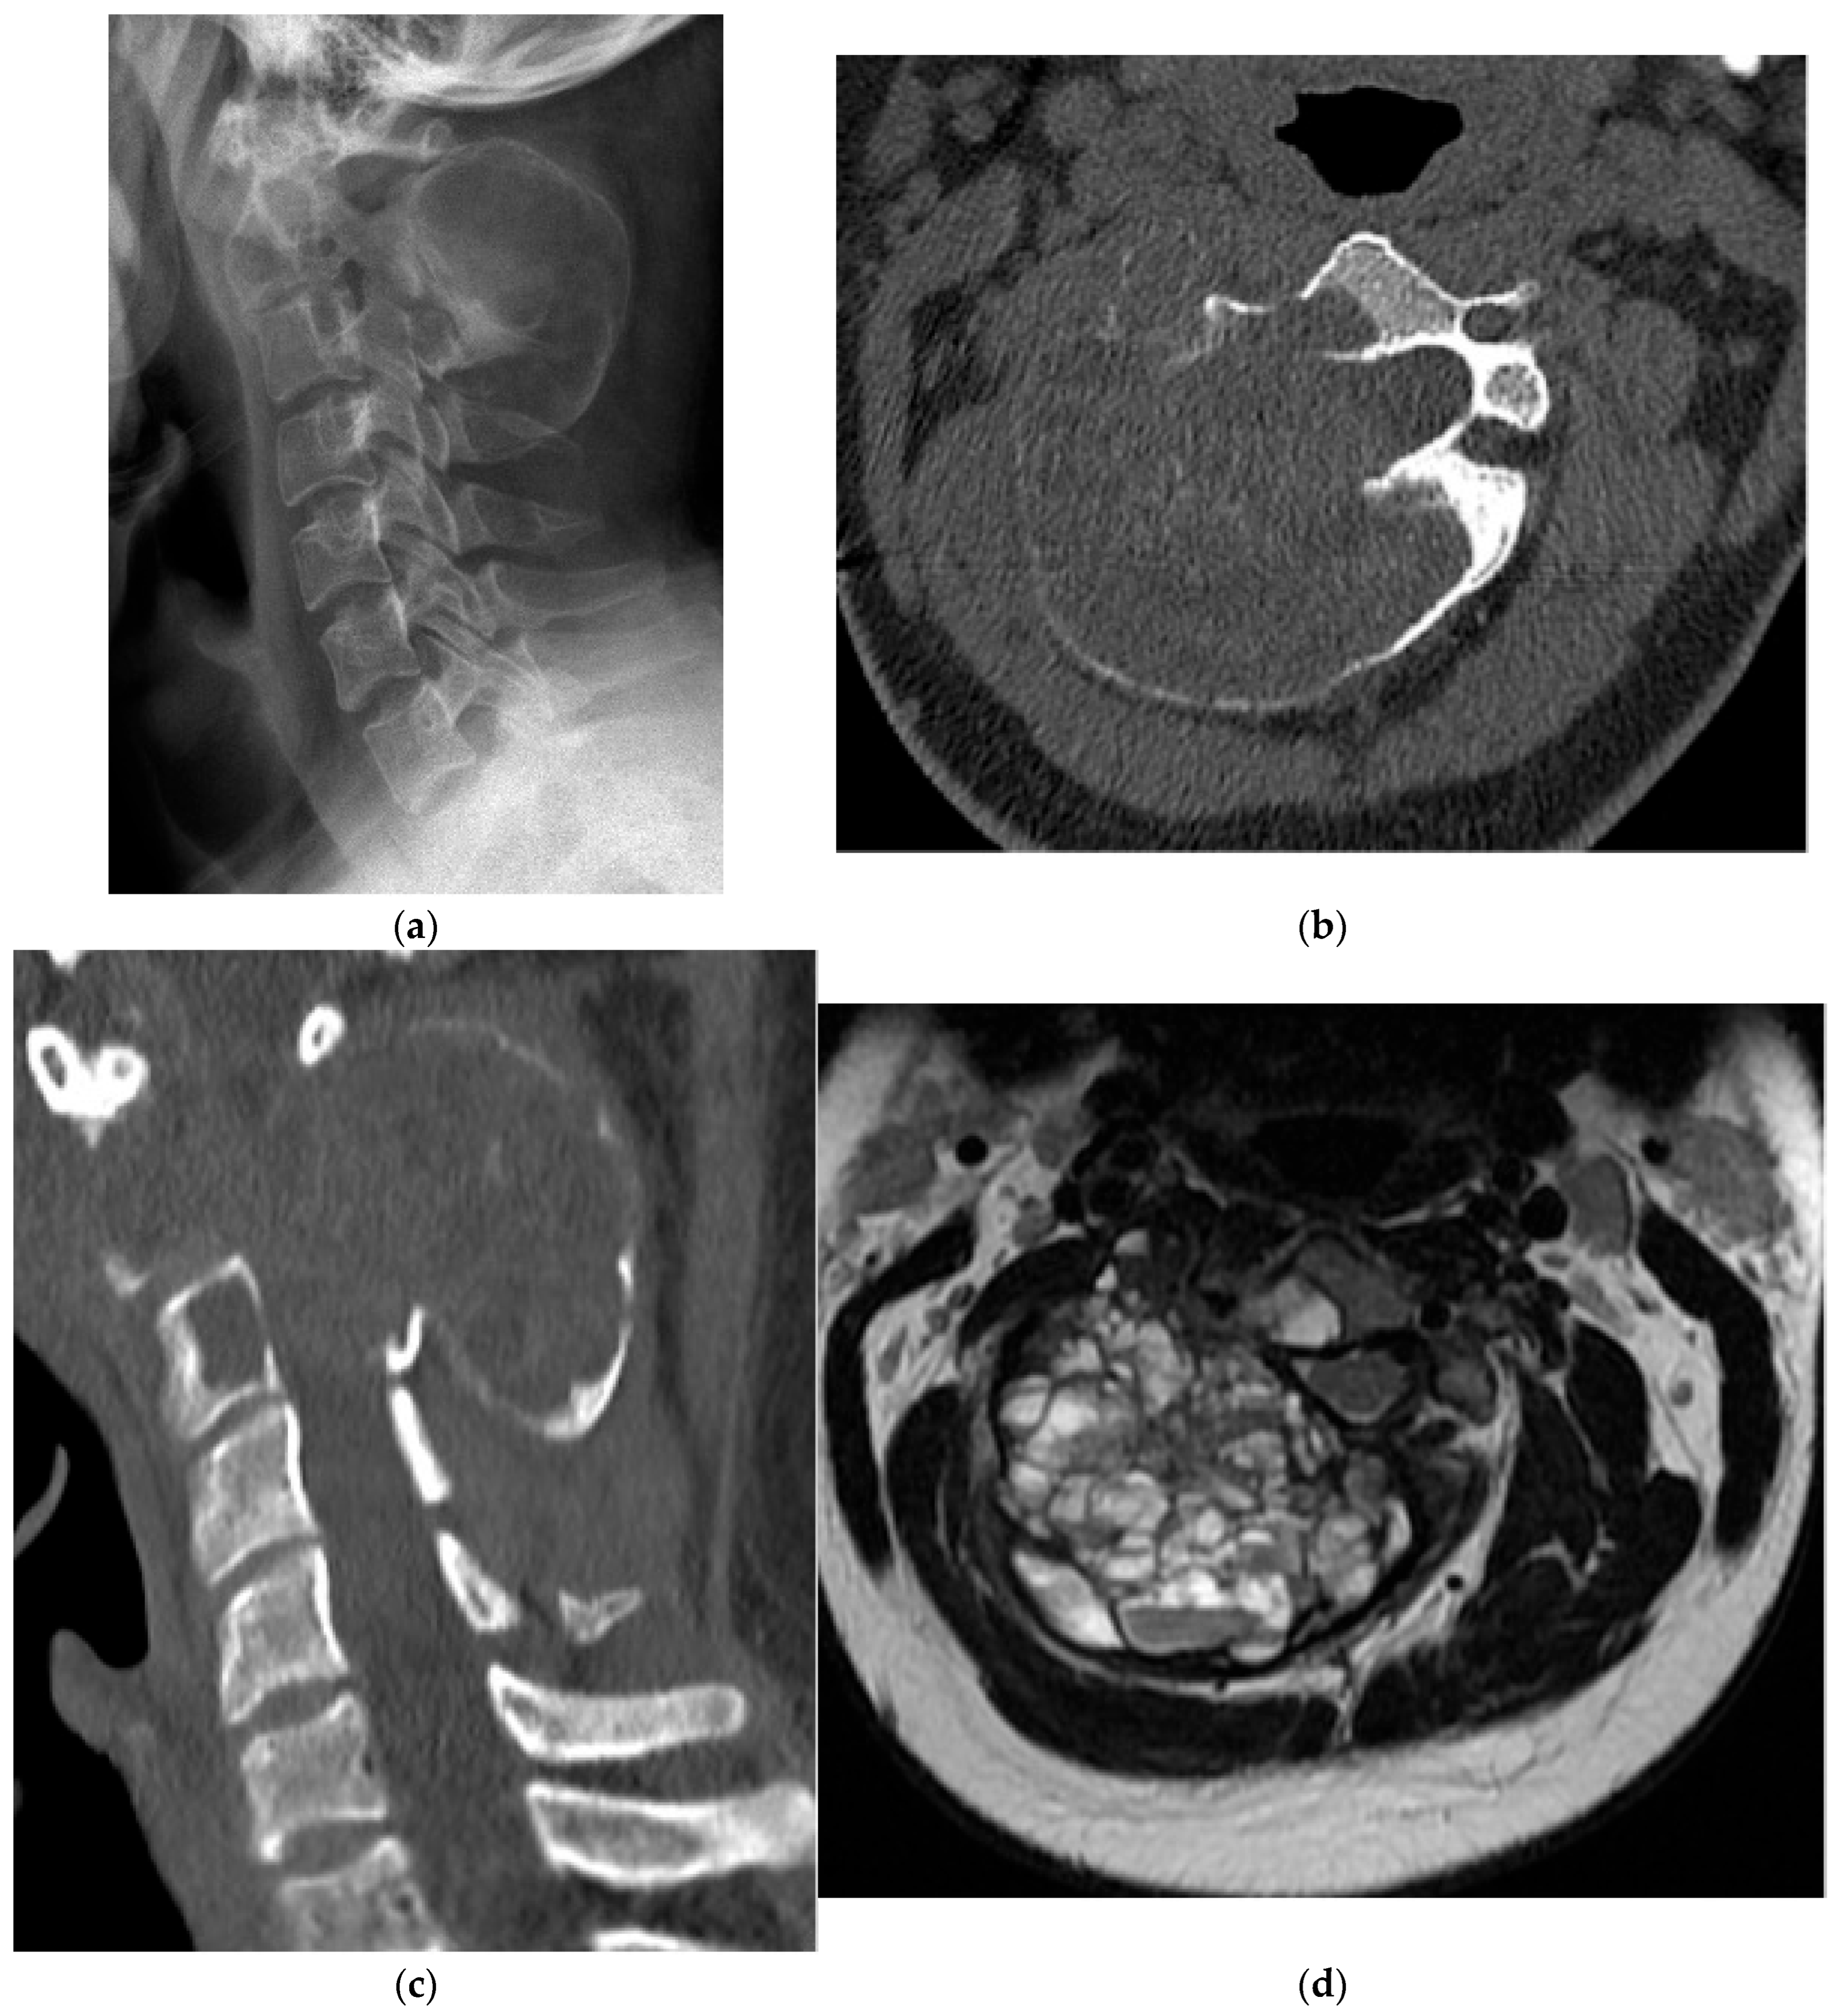

2.3.2. Chordoma

- Barber, S.M.; Sadrameli, S.S.; Lee, J.J.; Fridley, J.S.; Teh, B.S.; Oyelese, A.A.; Telfeian, A.E.; Gokaslan, Z.L. Chordoma—Current Understanding and Modern Treatment Paradigms. J. Clin. Med. 2021, 10, 1054. [Google Scholar] [CrossRef]

- Pennington, Z.; Ehresman, J.; McCarthy, E.F.; Ahmed, A.K.; Pittman, P.D.; Lubelski, D.; Goodwin, C.R.; Sciubba, D.M. Chordoma of the Sacrum and Mobile Spine: A Narrative Review. Spine J. 2021, 21, 500–517. [Google Scholar] [CrossRef] [PubMed]

- Zuckerman, S.L.; Bilsky, M.H.; Laufer, I. Chordomas of the Skull Base, Mobile Spine, and Sacrum: An Epidemiologic Investigation of Presentation, Treatment, and Survival. World Neurosurg. 2018, 113, e618–e627. [Google Scholar] [CrossRef]

- Das, P.; Soni, P.; Jones, J.; Habboub, G.; Barnholtz-Sloan, J.S.; Recinos, P.F.; Kshetry, V.R. Descriptive Epidemiology of Chordomas in the United States. J. Neurooncol. 2020, 148, 173–178. [Google Scholar] [CrossRef]

- Lee, S.H.; Kwok, K.Y.; Wong, S.M.; Chan, C.X.J.; Wong, Y.T.; Tsang, M.L. Chordoma at the Skull Base, Spine, and Sacrum: A Pictorial Essay. J. Clin. Imaging Sci. 2022, 12, 44. [Google Scholar] [CrossRef] [PubMed]